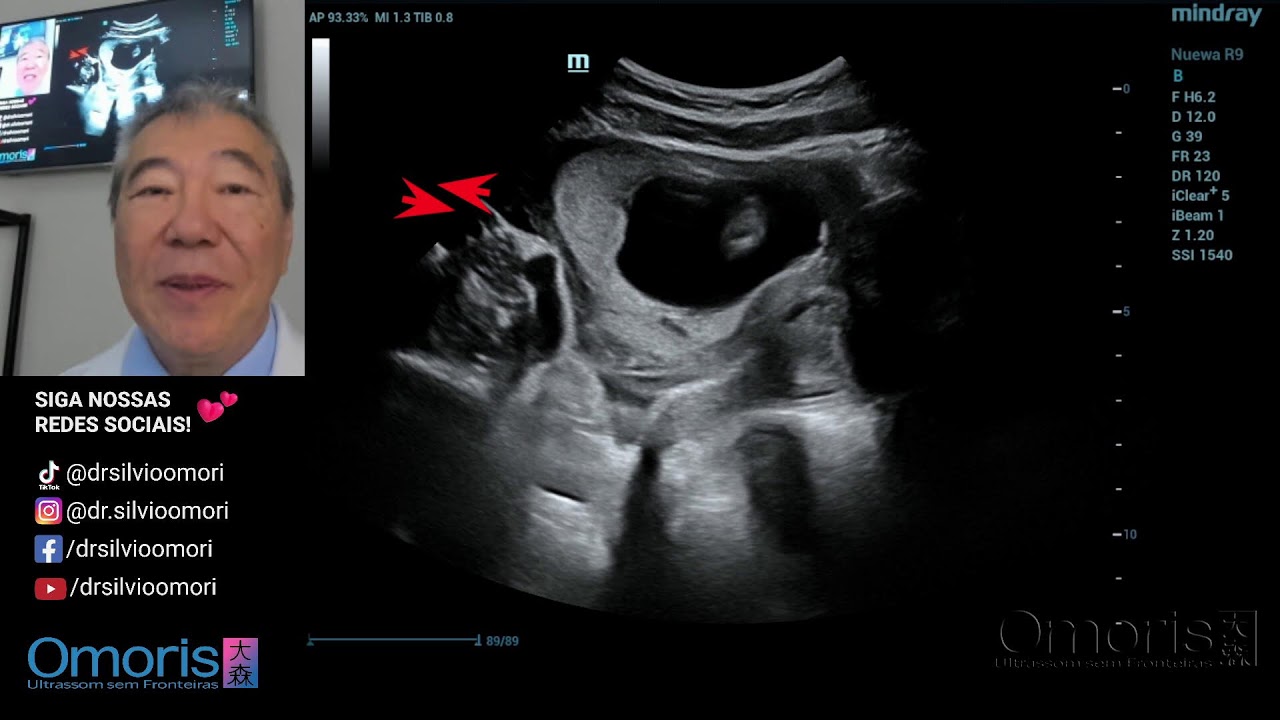

CHÁ REVELAÇÃO - 16s

Автор: Dr. Silvio Omori

Описание: Dr. Silvio Takao Omori CRM-PR 8227 RQE 27208

#gravidez #gestante #ultrassom #gestacao #sexagemfetalrimeiroDr. Silvio Takao Omori CRM-PR 8227 RQE 27208